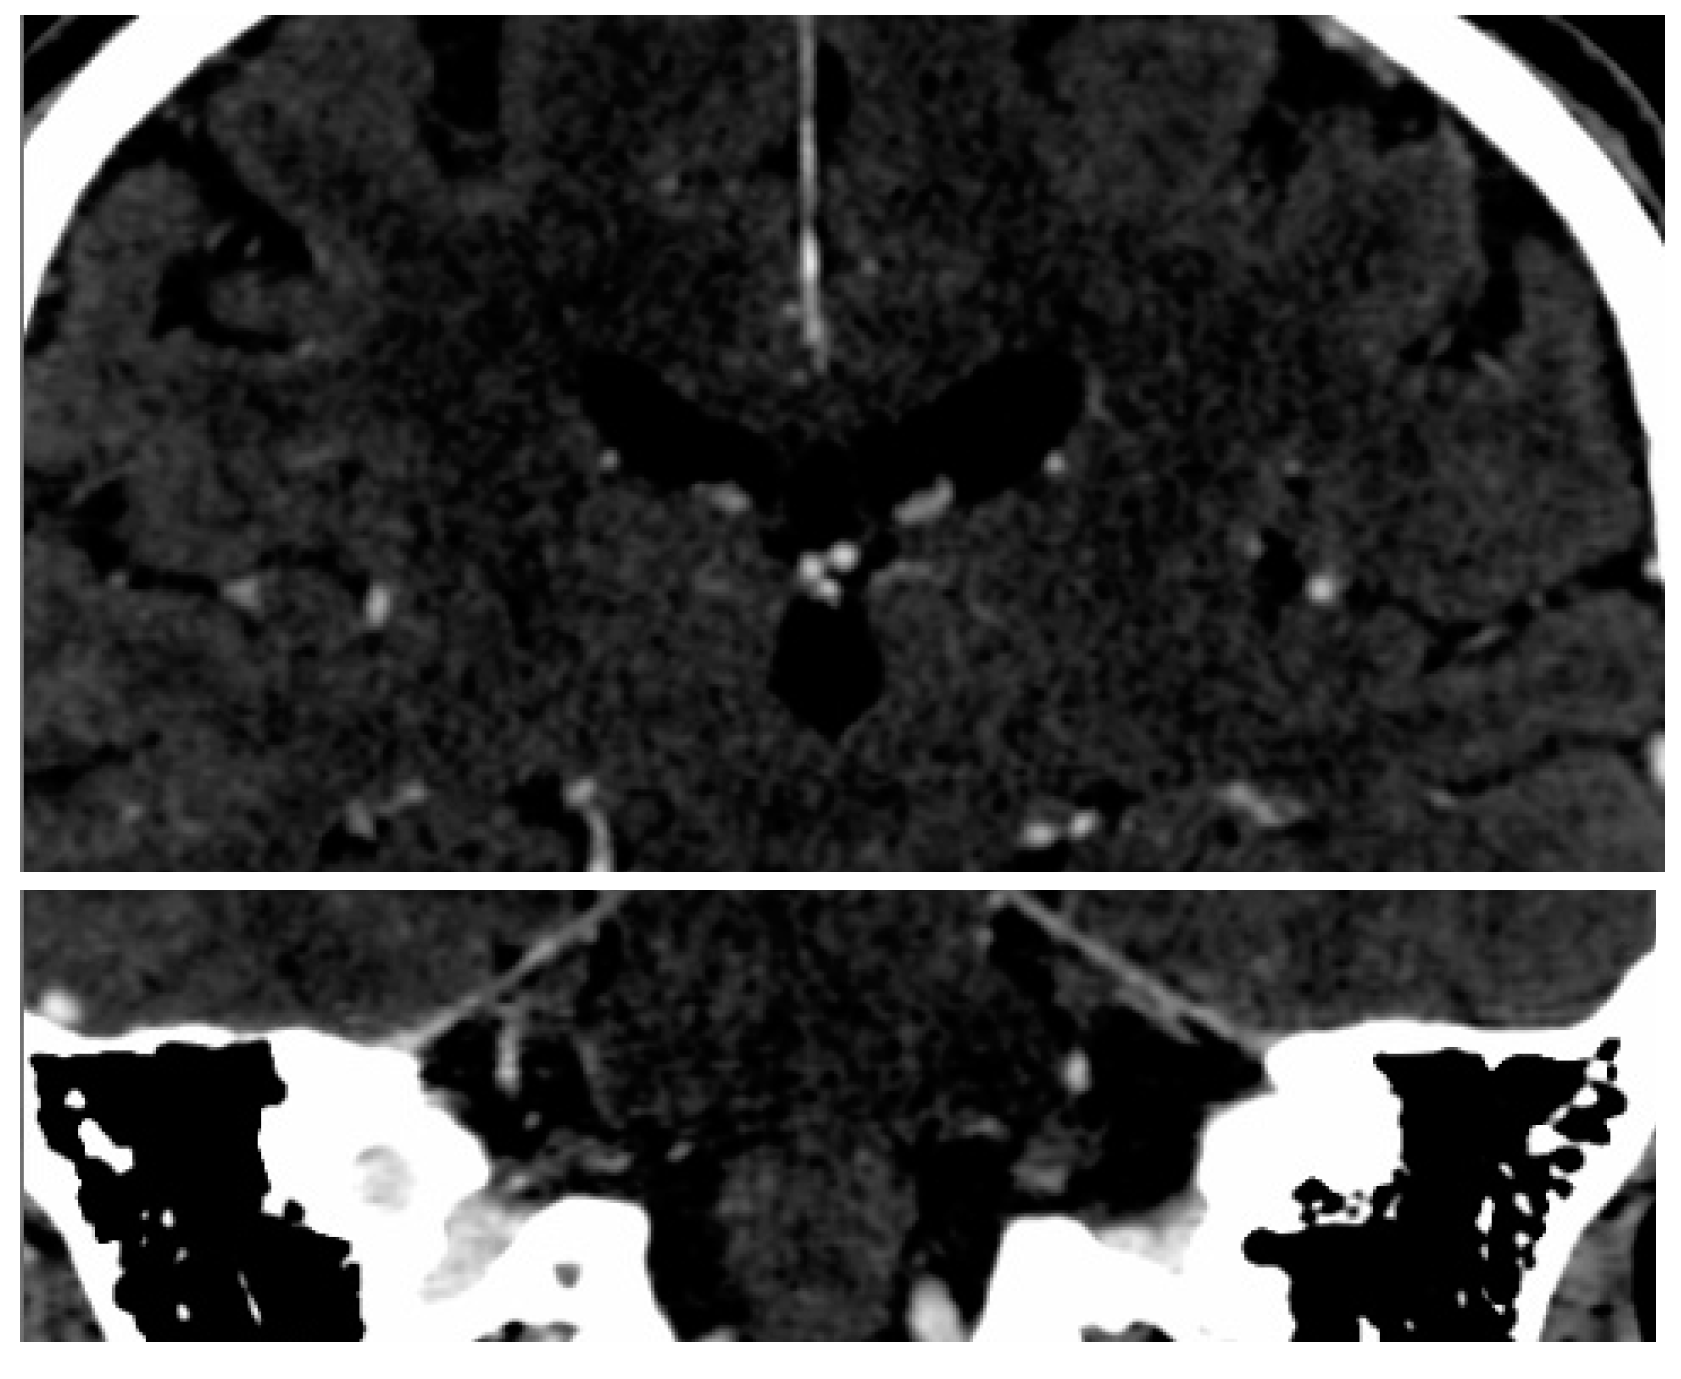

2.2. Imaging Protocol

2.3. SSA Software